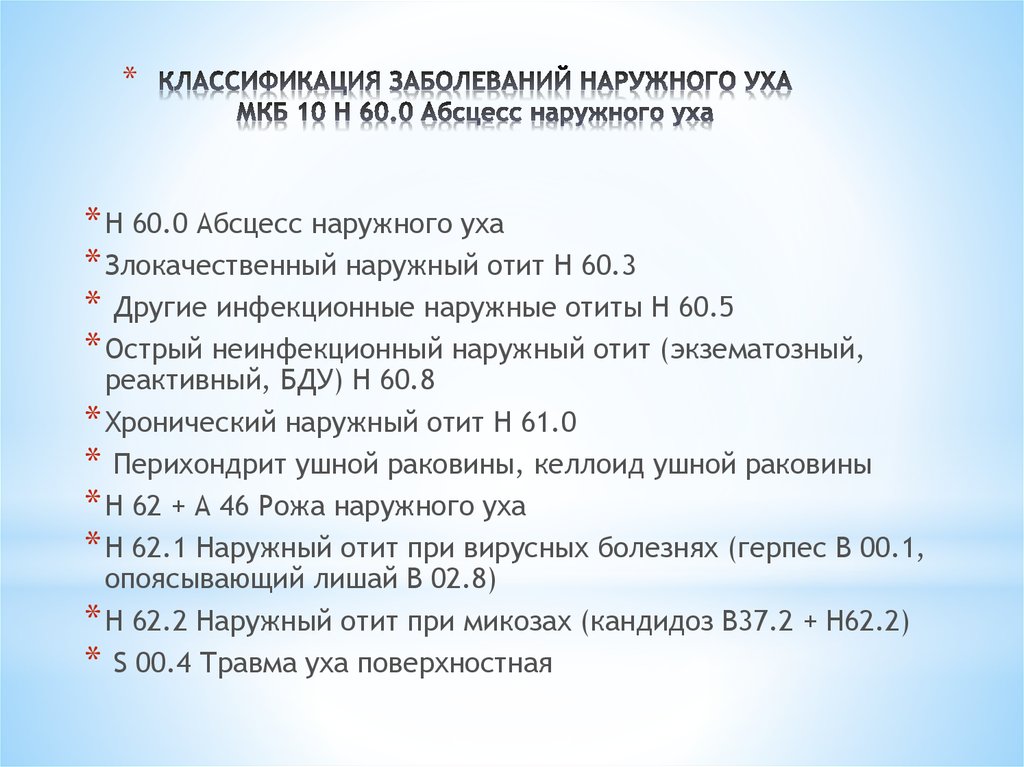

Код мкб 10 атерома головы

Код мкб 10 атерома головы 109 фото